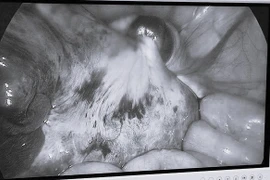

Co thắt tâm vị là một trong các bệnh rối loạn vận động thực quản, gây nuốt nghẹn, nôn ói... Nội soi Heller là phẫu thuật ít xâm lấn, thành công cao, đồng thời tạo van chống trào ngược giúp cải thiện chất lượng cuộc sống bệnh nhân.